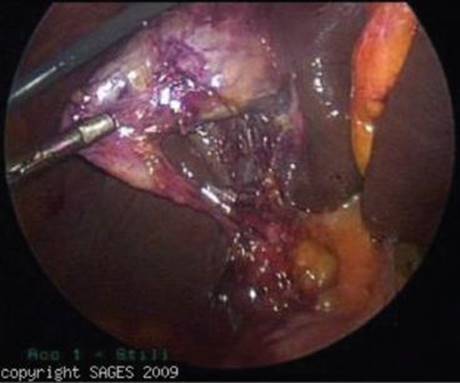

Once all ports are placed, the fundus of the gallbladder is retracted toward the abdominal wall and superiorly over the liver, and the peritoneum is dissected from the gallbladder neck. Dissection should be carried out from the gallbladder neck to the common bile duct in order to gain the critical view of safety (Figure 3). The critical view is achieved by clearing all fat and fibrous tissue in Calot’s triangle, after which the cystic structures can be clearly identified, occluded, and divided. This helps to avoid bile duct injuries and failure to successfully create this view is an indication for conversion to an open cholecystectomy.

FIGURE 3 • Critical view during laparoscopic cholecystectomy. Note the clear delineation of the junction of the cystic duct with the gallbladder as well as the clear space between the gallbladder and liver, devoid of any other structure other than the cystic artery.